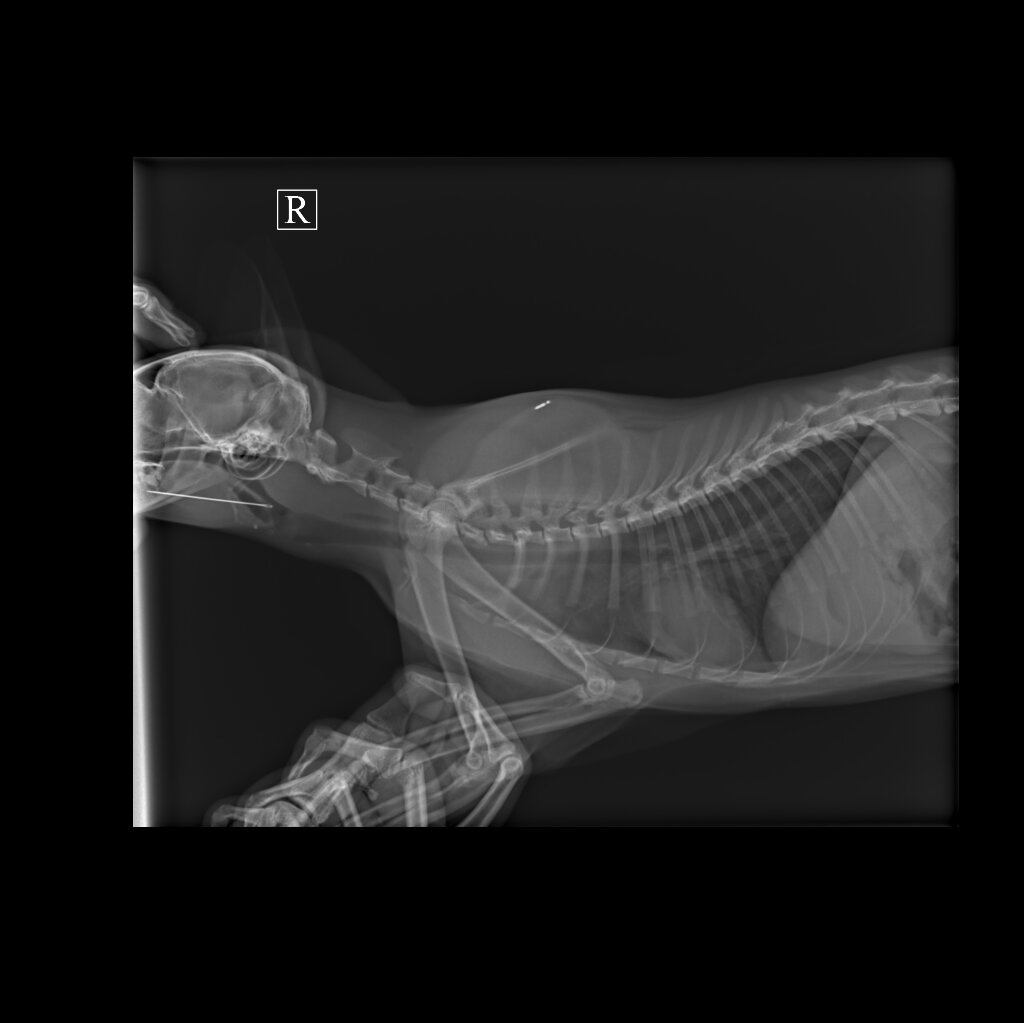

Макароша поступила с жалобами от владельцев: не ест, не ходит в лоток, прячется, почти не двигается.

📋 Обследование показало, что в пищеводе — металлическая игла, которая проткнула стенку пищевода.

Эксперт Соболев Александр Васильевич аккуратно извлёк инородное тело, жизнь Макароше удалось спасти.